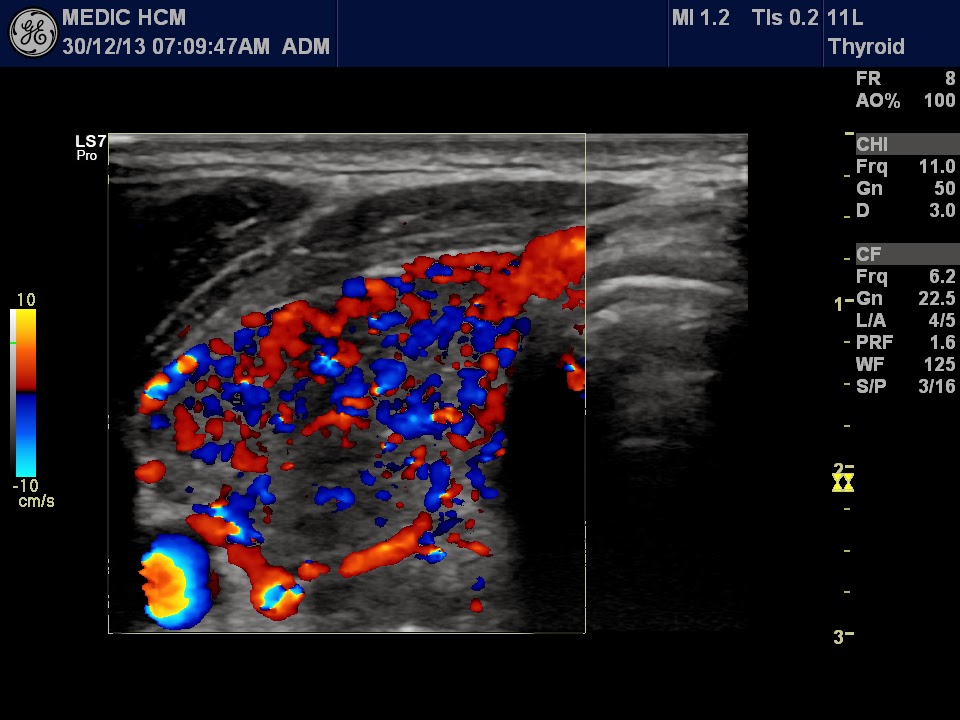

Graves' Disease Thyroid Color-Flow Doppler Ultrasonography ...

Thyroid Color-Flow Doppler Ultrasonography Assessment: Review Article. Health, 6, non-invasive and radiation free method, providing initial diagnosis and patients with GD follow up. Thyroid gland ultrasound examination performed in high frequency equipment ... Fetch Full Source